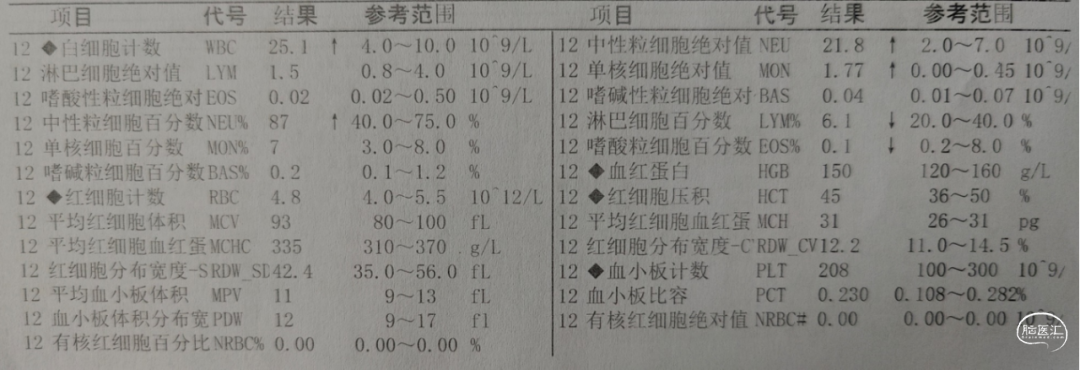

入院检查

![]()

入院化验

积极纠正凝血功能:氨甲环酸1g